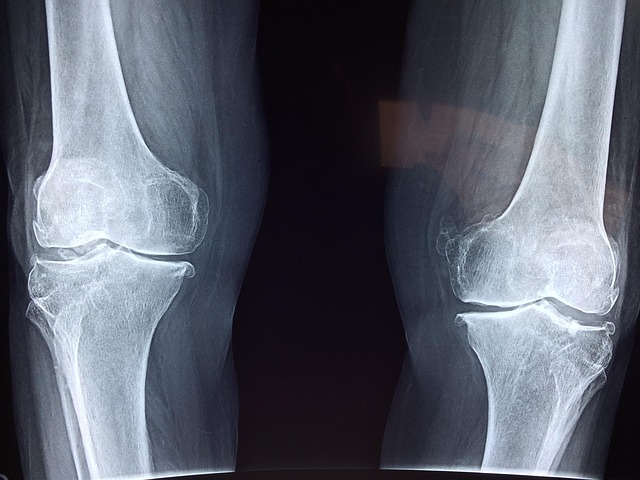

관절은 뼈와 뼈가 만나는 부위로, 충격을 흡수하고 움직임을 부드럽게 해주는 역할을 합니다. 이때 중요한 것이 바로 관절 사이를 감싸고 있는 연골입니다. 연골은 말랑말랑한 조직으로, 마찰을 줄이고 무게를 분산시켜 관절이 손상되지 않도록 도와줍니다. 하지만 나이가 들면서 연골은 점점 얇아지고, 탄력을 잃으며, 결국에는 퇴화하게 됩니다. 이러한 연골퇴화는 관절염이나 통증의 주요 원인이 됩니다. 연골이 퇴화하는 원인은 다양합니다. 첫 번째는 노화입니다. 연령이 증가하면서 연골을 구성하는 콜라겐과 수분 함량이 줄어들어 자연스럽게 닳기 쉽습니다. 두 번째는 과도한 체중입니다. 특히 무릎 관절은 체중의 3~5배 이상의 하중을 받기 때문에 비만한 경우 연골이 훨씬 더 빠르게 마모됩니다. 세 번째는 반복적인 사용입니다. 특정 관절을 지속적으로 사용하는 직업군이나 운동 선수는 연골에 지속적인 마찰이 가해지며 퇴행성 변화가 빨리 일어날 수 있습니다. 네 번째는 잘못된 자세입니다. 다리를 꼬고 앉는 습관, 오래 서 있는 자세, 하이힐 착용 등은 관절에 부담을 주는 자세로, 연골에 불균형한 압력을 유발합니다. 다섯 번째는 염증입니다. 류마티스 관절염처럼 자가면역 질환이 있거나, 잦은 부상 후 회복이 미진한 경우 관절 내 염증이 발생해 연골 파괴를 촉진합니다. 결국 연골이 퇴화하면 관절 간격이 좁아지고, 마찰이 커지며, 뼈끼리 직접 부딪히는 통증이 발생하게 됩니다. 따라서 연골퇴화원인을 정확히 이해하고, 위험 요인을 줄이는 것이 관절건강지키기의 첫 걸음입니다. 생활습관을 조절하고, 무리한 관절 사용을 피하며, 평소 올바른 자세를 유지하는 것이 연골 보호에 매우 효과적입니다.